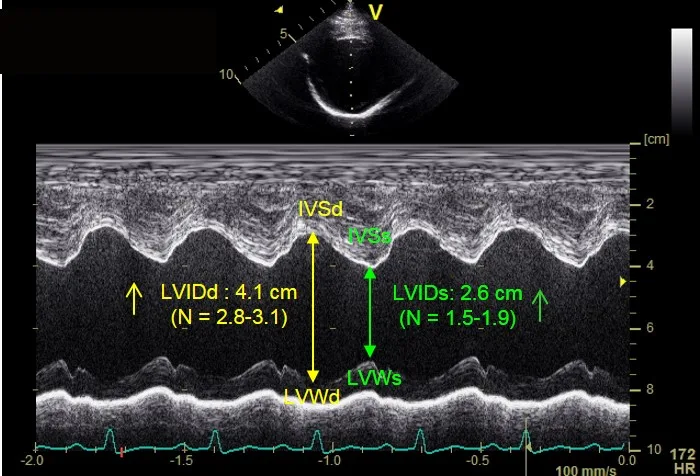

Stage B2 DCM

This Doberman Pinscher was diagnosed with Stage B2 DCM based on abnormal left ventricular measurements. Figure 4A shows left ventricular dimensions at the upper end of published normal for the breed during diastole (LVIDd) and an abnormal end systolic dimension during systole (LVIDs).

IVSd = interventricular septum in diastole, IVSs = interventricular septum in systole, LVIDd = left ventricular internal dimension in diastole, LVIDs = left ventricular internal dimension in systole, LVWd = left ventricular posterior wall in diastole, LVWd = left ventricular posterior wall in diastole, LVWs = left ventricular posterior wall in systole

The fractional shortening between these cases is similar (15% for Figure 3A and 11% for the Figure 4A); however, the LVIDd and LVIDs are extremely different as compared with normal values for the breed.